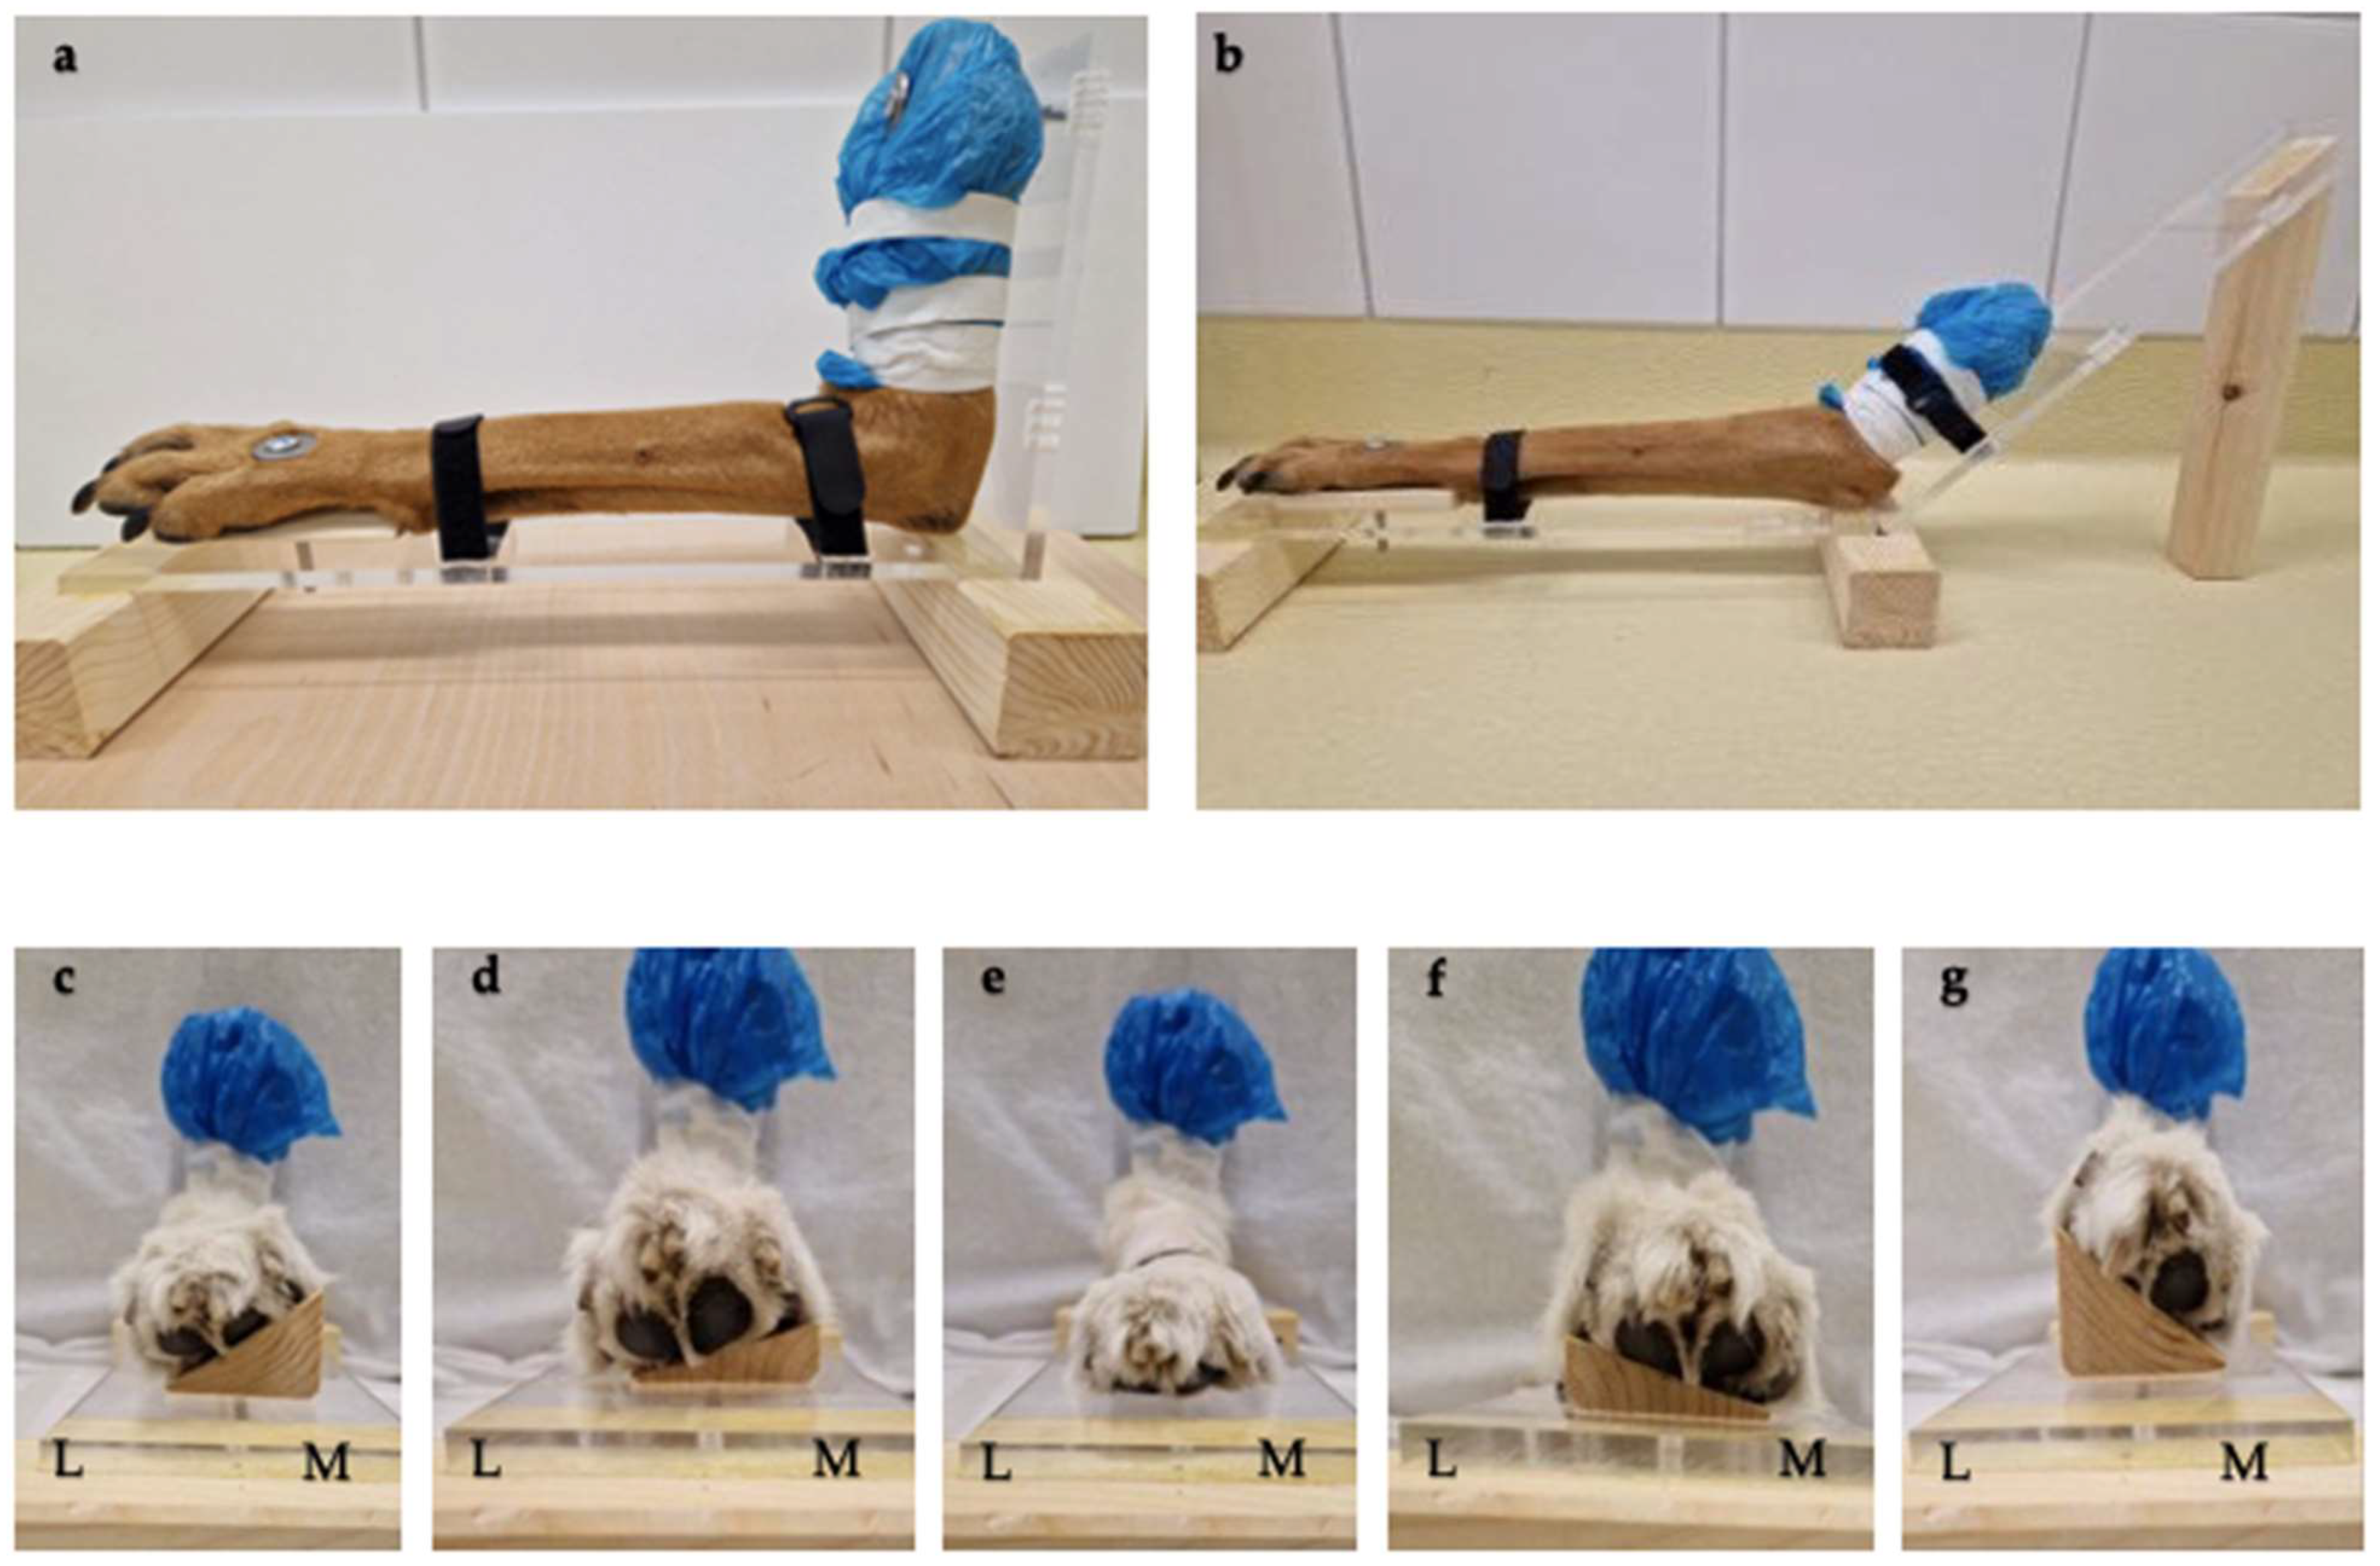

2.2. Positioning Aids

2.3. Image Acquisition